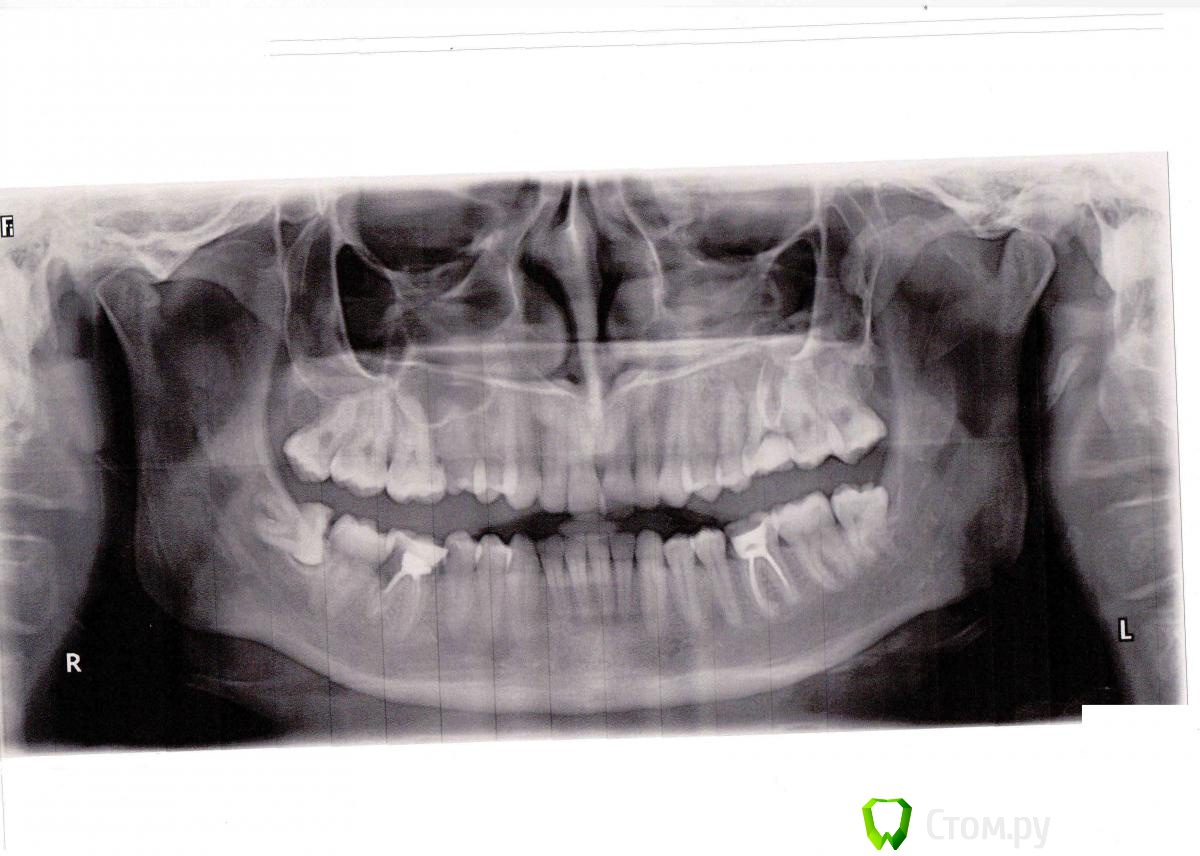

IvanK Опубликовано 6 февраля, 2014 Поделиться Опубликовано 6 февраля, 2014 http://s005.radikal.ru/i212/1402/ca/132f15f1c4ad.jpg Ссылка на комментарий

IvanK Опубликовано 6 февраля, 2014 Поделиться Опубликовано 6 февраля, 2014 Здравствуйте, насколько травматичным будет удаление 48 зуба в умелых руках - не травматично,ищите Врача, для которого данное удаление - рутина. период восстановления как после обычного удаления, возможен отекСоветовал бы удалить все 8ки, _+ 46консультация ортодонтаповторное лечение с последующим протезированием коронками 26,36 3 Ссылка на комментарий

IvanK Опубликовано 6 февраля, 2014 Поделиться Опубликовано 6 февраля, 2014 26 лечил только в декабре тогда давайте новый снимок 46 мне предлагали лечить заново каналы и ставить коронку, судя по снимку пол корня там уже нет 1 Ссылка на комментарий

max2141 Опубликовано 12 июня, 2014 Автор Поделиться Опубликовано 12 июня, 2014 Ещё раз здравствуйте, уважаемые доктора!Обратился к другому терапевту за лечением 4.5, помимо этого зуба врач обратил внимание на некоторую болезненность зуба 2.6 при постукивании. Вкладка там стоит с февраля 2014г. Эта болезненность норма и пройдет со временем или требуется что-то делать? Также доктор рекомендовал удаление 1.5 из-за пульпита и разворота зуба на 90 градусов - это оправданно?Заранее благодарю. Ссылка на комментарий

red_butler Опубликовано 13 июня, 2014 Поделиться Опубликовано 13 июня, 2014 Зуб под с вкладкой болеть с февраля не должен. Временной коронки нет? Сделайте фото 1.5 зуба, пульпит и дистопия не являются сами по себе показаниями к удалению 1 Ссылка на комментарий

faity Опубликовано 13 июня, 2014 Поделиться Опубликовано 13 июня, 2014 согласен, без снимков ловить нечего, делайте рентген 1.5, 2.6- посмотрим Ссылка на комментарий